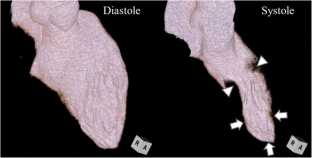

Fig. 2

Four-dimensional left ventricular myocardial function analysis provided a more accurate representation of the myocardial dynamic motion, and showed apical hypokinesis and a hypercontractile base during systole. (AVI 594 kb)